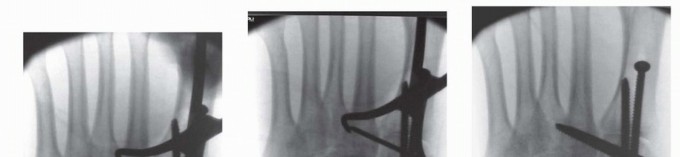

3. ## Provisional Reduction and Definitive Stabilization

First Tarsometatarsal Joint

The provisional reduction begins medially at the first tarsometatarsal joint if injured. Although the exact reduction maneuver may vary depending on the injury pattern, the first metatarsal is typically supinated (externally rotated) relative to the medial cuneiform.

Correction of this rotational deformity is crucial in restoring the medial column and the weight-bearing

function of the first ray. The reduction of the remaining midfoot joints depends on an anatomic reduction of the first tarsometatarsal joint.

The provisional reduction is held with a 2.0-mm Kirschner wire and confirmed under fluoroscopy (

TECH FIG 3A

).

TECH FIG 3 • Reduction and stabilization of first tarsometatarsal joint. A. Provisional reduction. B. Distal to proximal screw. C. Proximal to distal screw. D. Long bicortical trajectory of screws for enhanced stability. Definitive stabilization is then obtained at the first tarsometatarsal joint with 3.5-mm solid cortical position screws (

TECH FIG 3B-D

The first screw is placed from distal to proximal, starting at the dorsal crest and distal to the metaphyseal-diaphyseal junction, and is angled toward the plantar-proximal cortex of the medial cuneiform; this screw is generally 45 to 50 mm long.

A second screw is placed from proximal to distal starting at the edge of the naviculocuneiform joint and similarly angled to exit at the plantar cortex distal to the metaphyseal-diaphyseal junction. This screw typically measures 40 to 45 mm.

In a primary arthrodesis, these screws are placed in lag fashion.

For larger patients, 4.0-mm cortical screws may be used for further stability.